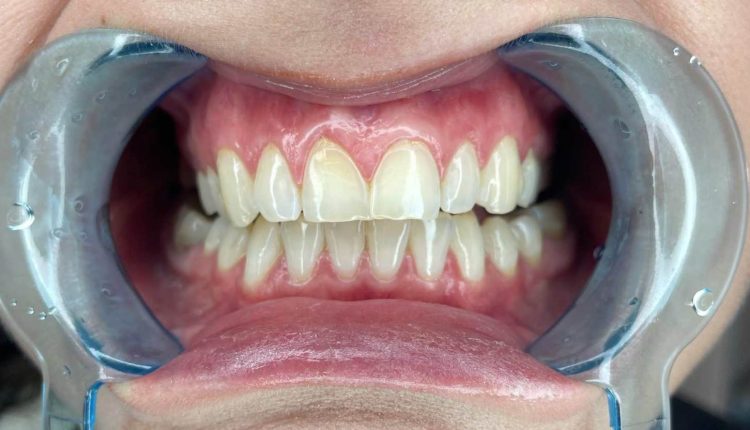

تراجع اللثة مشكلة تقلق كثير من الناس، لا سيما الشباب والفتيات في مقتبل العمر. حينما تنحسر اللثة وتبدأ جذور الأسنان في الظهور خاصةً في الأسنان الأمامية، يبدأ المرء في القلق على أسنانه وعلى شكل ابتسامته.

يحدث تراجع اللثة عندما تنكمش الأنسجة المحيطة بالأسنان تدريجياً وتتركها مكشوفة أكثر من المعتاد وأحيانًا تبدأ الجذور في الظهور للعيان مما يؤثر على الناحية الجمالية خاصة عند الابتسام أو أثناء الكلام.

وقد يشكو المريض من زيادة طول الأسنان أو ظهور الجذور خاصةً في الأسنان الأمامية، أو يشعر ببعض الحساسية عند تناول شيء ساخن أو مثلج.